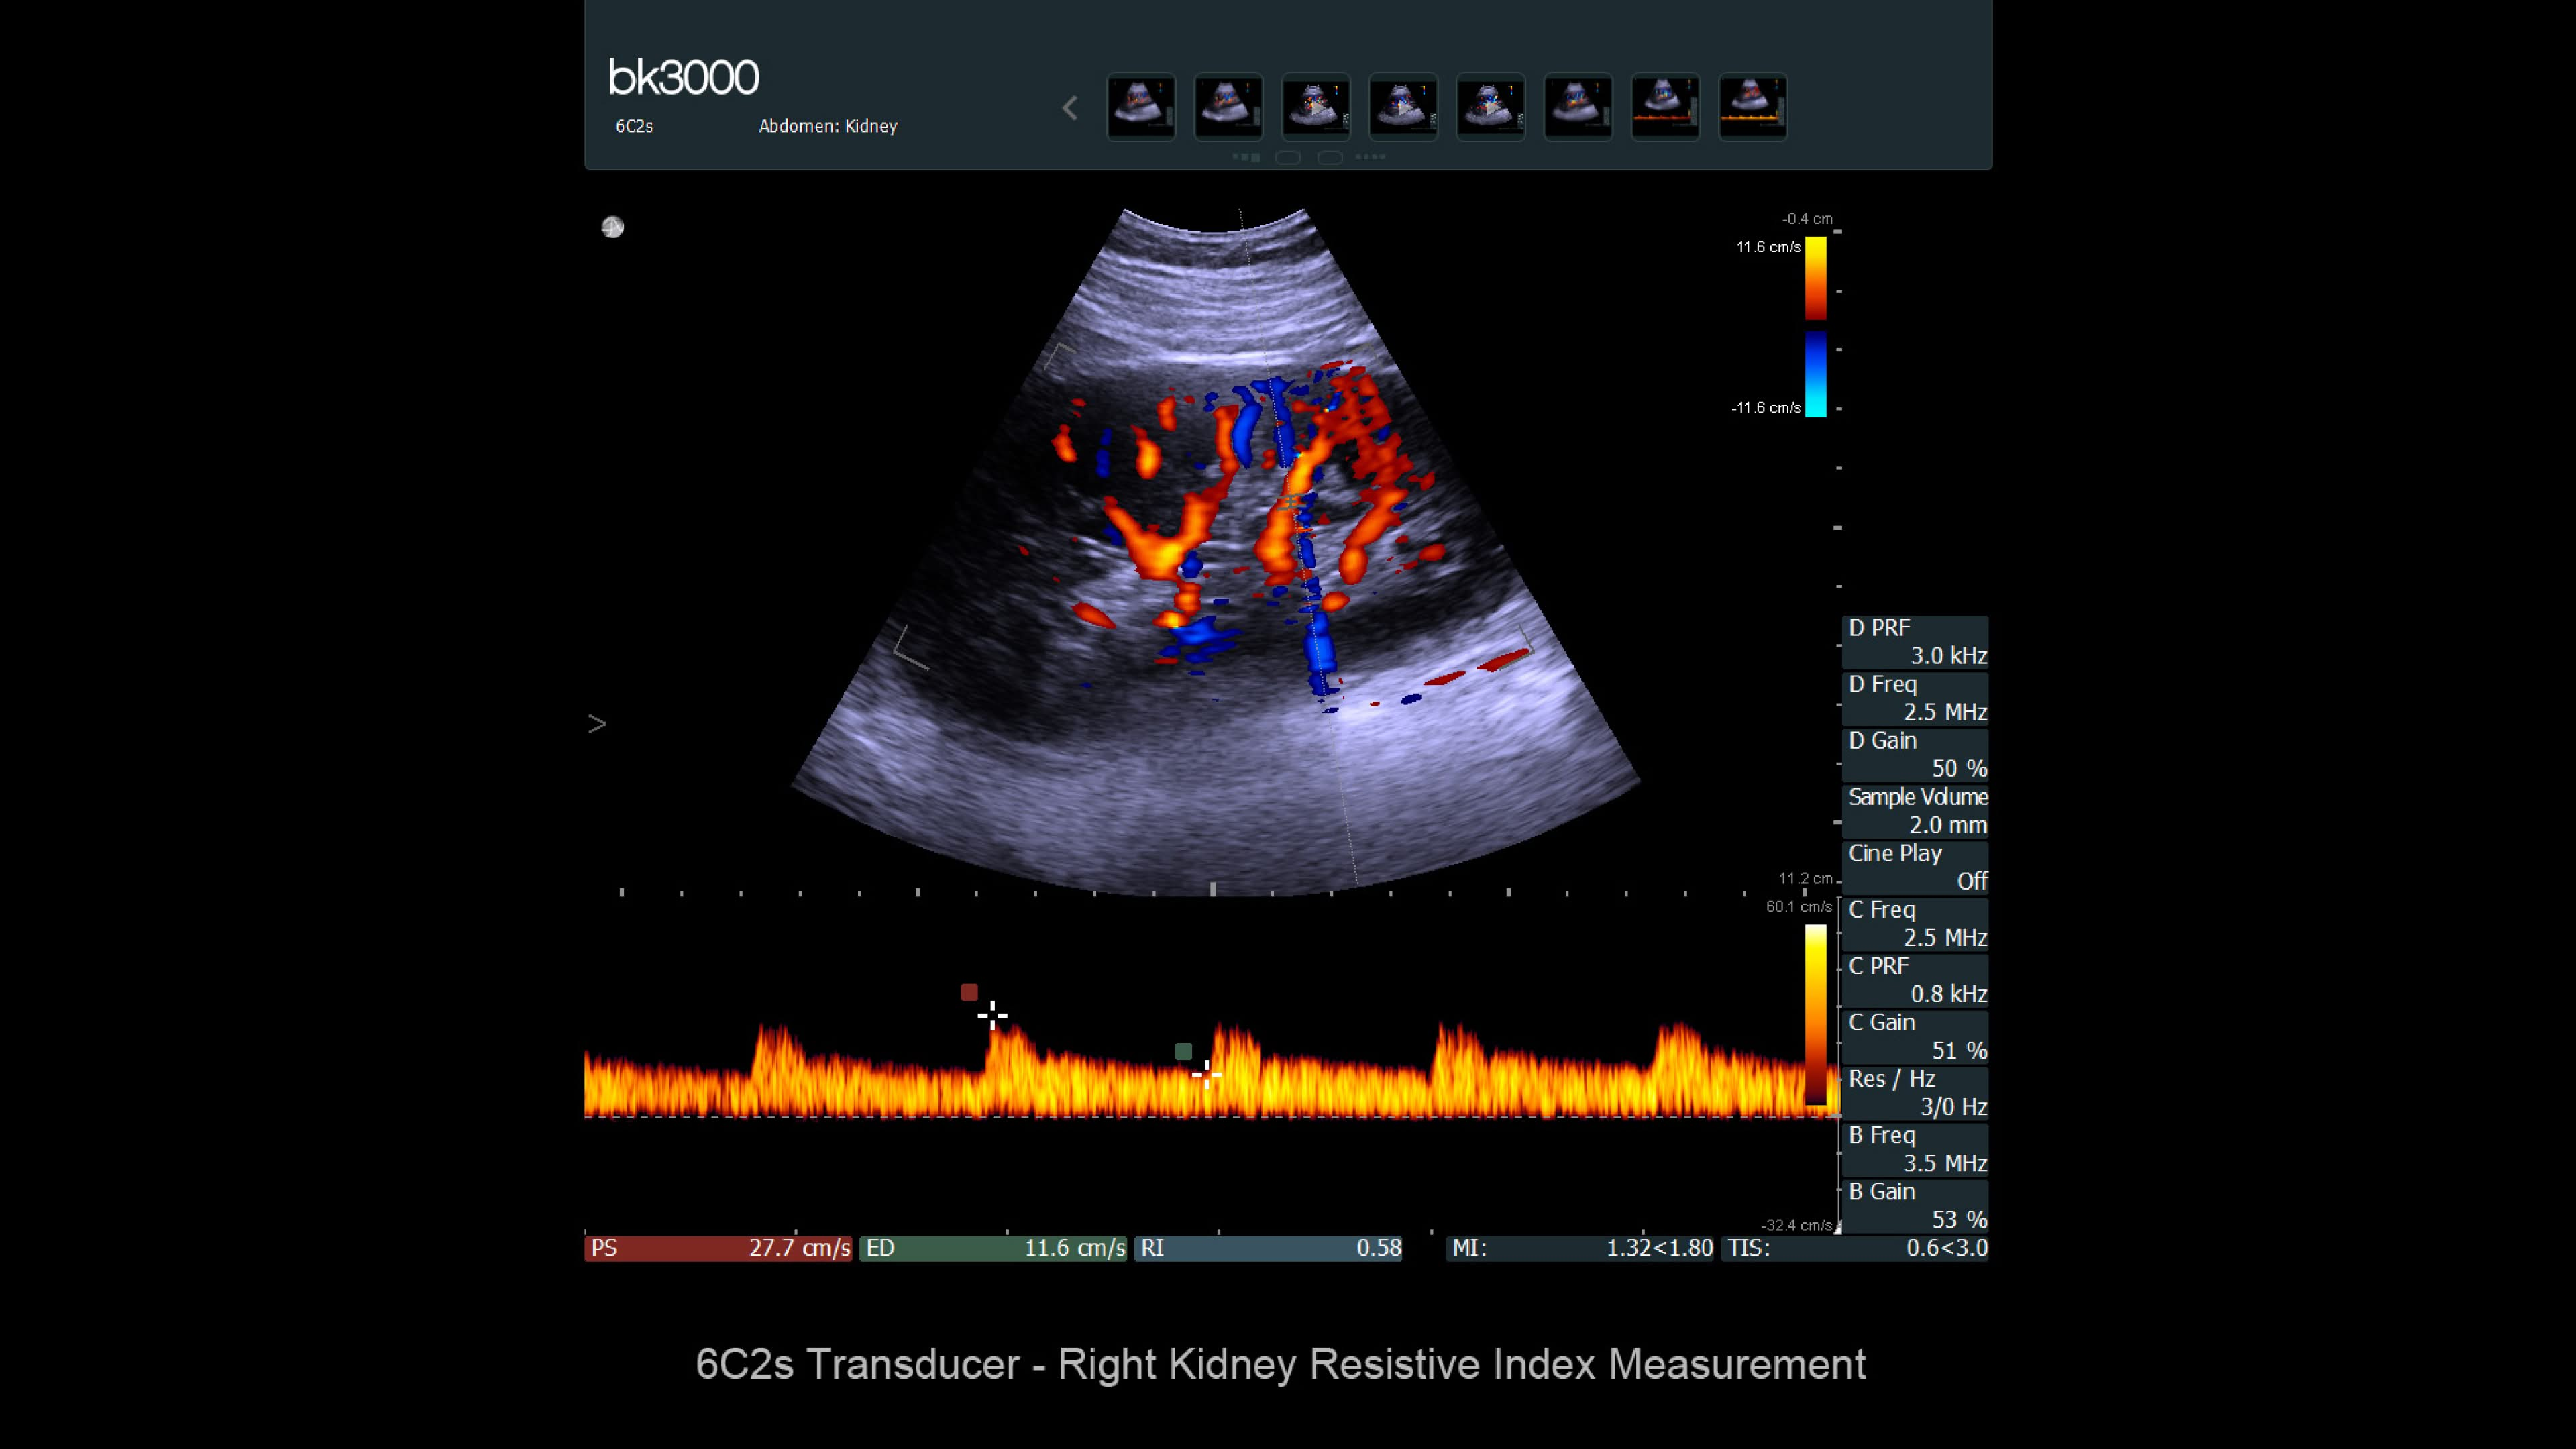

Comprehensive kidney imaging solutions

Ultrasound for kidney

Ultrasound provides detailed information for kidney imaging, measurement, and biopsies. The bk3000 and bkSpecto systems help visualize fine anatomical details, see vascularization, measure blood flow, and locate kidney stones. The bkActiv, our flagship system, offers next-level imaging for prostate, renal, kidney, and bladder imaging, with sensitive Doppler for blood flow. Combined with sterilizable transducers, the bkActiv sets a new standard for surgical urology.